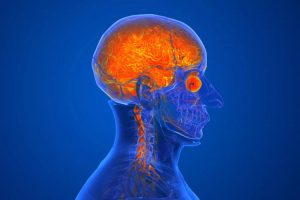

അമീബിക്ക് മെനിഞ്ചോ എൻസെഫലൈറ്റിസ് : സാധ്യമായ എല്ലാ വിദഗ്ധ ചികിത്സയും നൽകും പ്രദേശത്ത് പ്രതിരോധ പ്രവർത്തനങ്ങൾ ശക്തിപ്പെടുത്തി konnivartha.com: അമീബിക്ക് മെനിഞ്ചോ എൻസെഫലൈറ്റിസ് ബാധിച്ച് കോഴിക്കോട് മെഡിക്കൽ കോളേജ് സ്ത്രീകളുടേയും കുട്ടികളുടേയും ആശുപത്രിയിൽ ചികിത്സയിലുള്ള കുട്ടിയ്ക്ക് സാധ്യമായ എല്ലാ വിദഗ്ധ ചികിത്സയും... Read more »